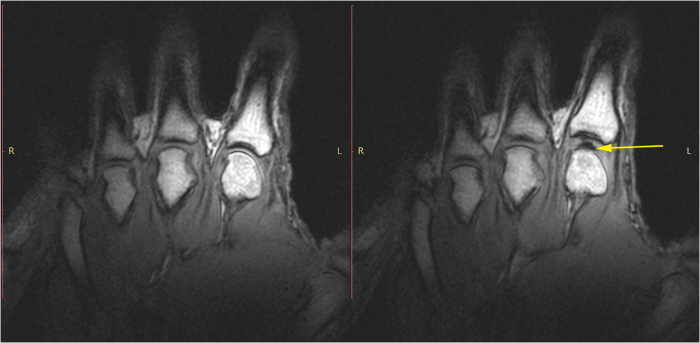

Статические снимки показали, что пястно-фаланговые суставы с ожидаемым отсутствием любой газовой полости до начала вытяжения сустава являются нормальными. После вытяжения на снимках видно, как внутри сустава появилось темное пространство (рис. 3).

На МРТ-съемке показана последовательность событий, описанная Roston B. и Haines W. (видео)